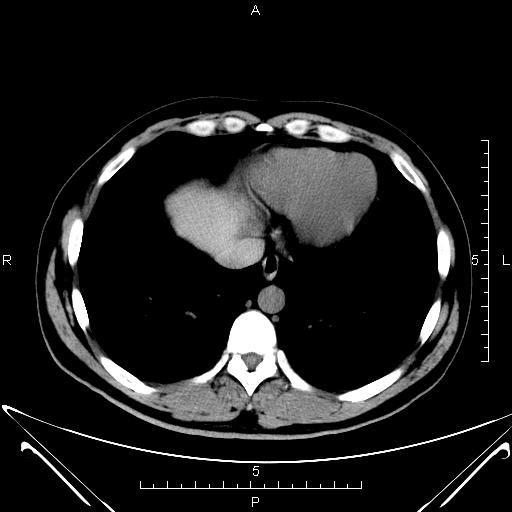

CT50260:上腹部CT

男,43岁,体检彩超发现肝右叶低回声结节,内可见斑点状强回声,后伴声影。

平衡期轻度强化,边缘强化,考虑炎性假瘤或炎性肌纤维母细胞瘤。

右肝后叶低密度小结节影,考虑血管瘤可能(动脉期无明显强化,门脉期病灶边缘强化),不典型小肝癌待除外。